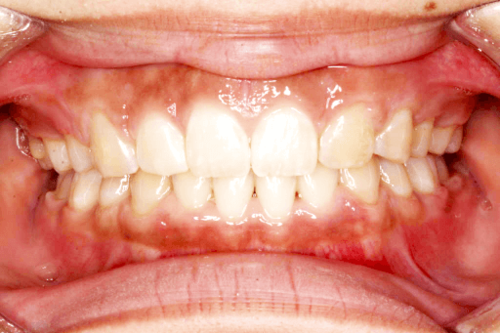

【BEFORE 正面】

ご相談内容:すきっ歯なので話がしづらい

(空隙歯列/くうげきしれつ)

矯正の種類:マウスピース型矯正『クリアコレクト』

矯正費用:88万円(税込)

矯正期間:40週

上唇小帯が原因で、歯が戻りやすい症例。そのため矯正治療後は、リテーナーの装着をして保定を長期間設けることできれいな歯並びを維持しています。